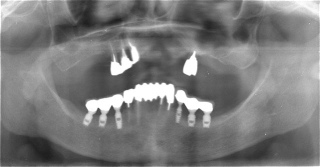

インプラント義歯 ミニインプラント症例

術前術前主訴-総入れ歯の安定が悪い 即時加重可能のミニインプラント使用した。 術前レントゲン術前レントゲン術前レントゲン CT撮影から3次元骨モデルを作成CT撮影から3次元骨モデルを作成CT撮影から3次元骨モデルを作成し埋入位置の確認 フィクスチャーを浸潤麻酔下で埋入フィクスチャーを浸潤麻酔下で埋入。歯茎を切らないので患者さんも非常に楽

4本埋入終了4本埋入終了4本埋入終了(このシステムは4本が絶対条件) 義歯の調整義歯の調整当日に義歯の調整に取りかかる。裏側より義歯をくりぬき維持部のカバー(ハウジング)を義歯の内面に埋め込む step1 義歯の調整義歯の調整当日に義歯の調整に取りかかる。裏側より義歯をくりぬき維持部のカバー(ハウジング)を義歯の内面に埋め込む step2 義歯の調整当日に義歯の調整に取りかかる。裏側より義歯をくりぬき維持部のカバー(ハウジング)を義歯の内面に埋め込む step3

義歯の調整義歯の調整当日に義歯の調整に取りかかる。裏側より義歯をくりぬき維持部のカバー(ハウジング)を義歯の内面に埋め込む step4 義歯の調整義歯の調整当日に義歯の調整に取りかかる。裏側より義歯をくりぬき維持部のカバー(ハウジング)を義歯の内面に埋め込む step5 義歯の裏側義歯の裏側義歯の裏側 装着後しっかり噛める様になる

術後レントゲン術後レントゲン術後レントゲン